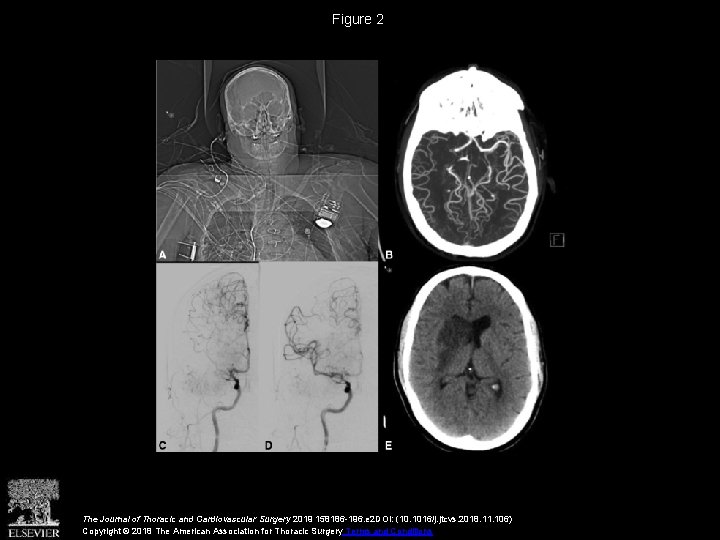

Figure 2 The Journal of Thoracic and Cardiovascular Surgery 2019 158186 -196. e 2

Figure 2 The Journal of Thoracic and Cardiovascular Surgery 2019 158186 -196. e 2 DOI: (10. 1016/j. jtcvs. 2018. 11. 106) Copyright © 2018 The American Association for Thoracic Surgery Terms and Conditions